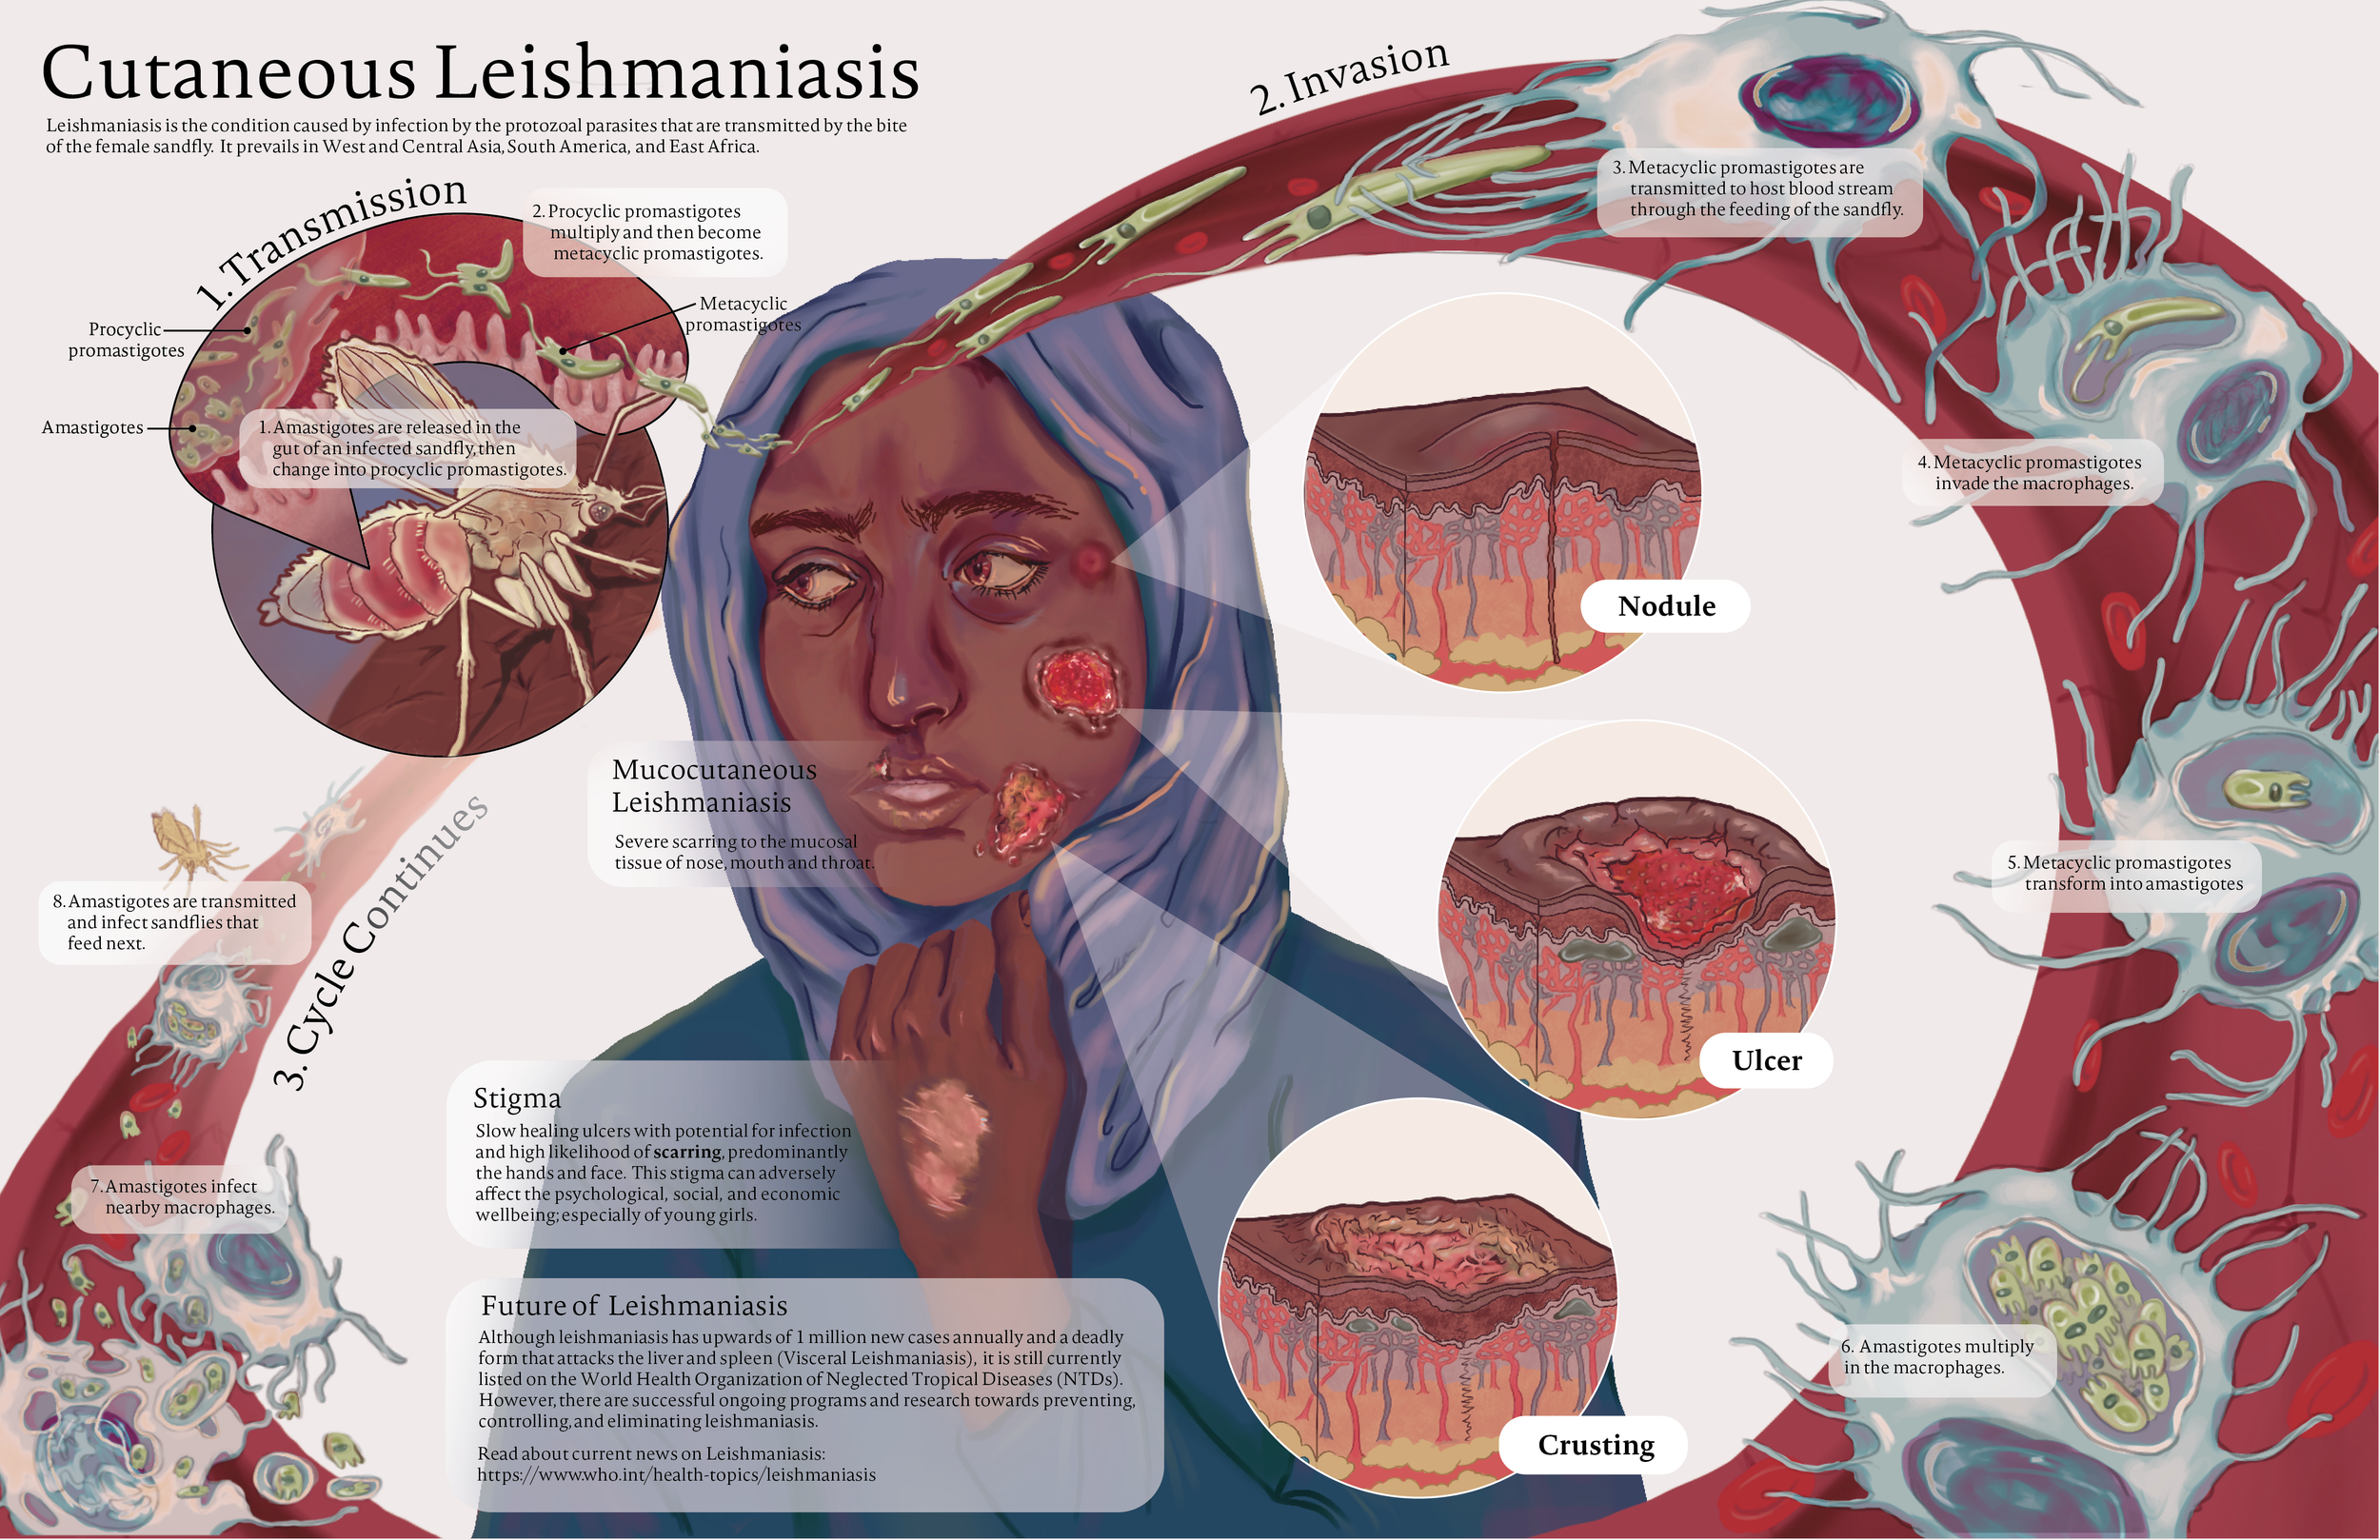

Craniosynostosis Care

Explore a curated collection of our past work, where imagination meets strategy. Each project reflects our drive to deliver thoughtful, effective solutions.

Series: Inclusive Anatomy